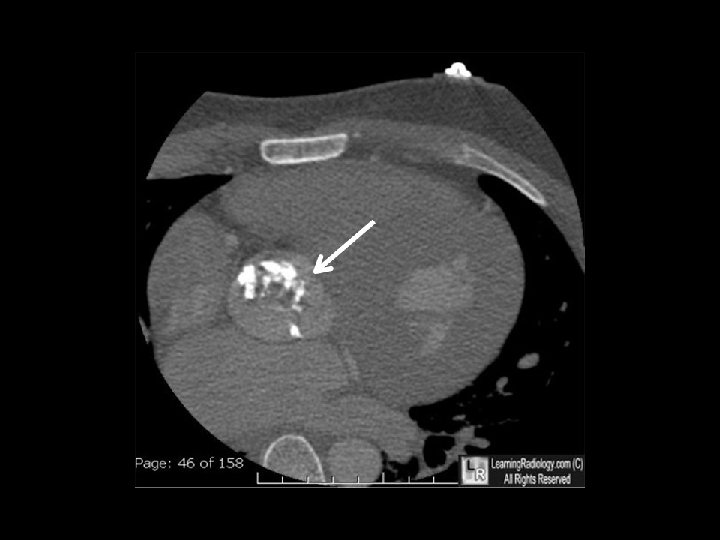

AORTIC STENOSIS CT • best method to assess annulus, aorta and calcium • assess GOA • assess coronaries • severity of AS. . < 700 AU. . excludes severe AS > 2000 AU. . severe AS > 1650. . optimal sensitivity & specificity • evaluation of prosthetic valve • planning TAVR CMR • assess myocardial fibrosis